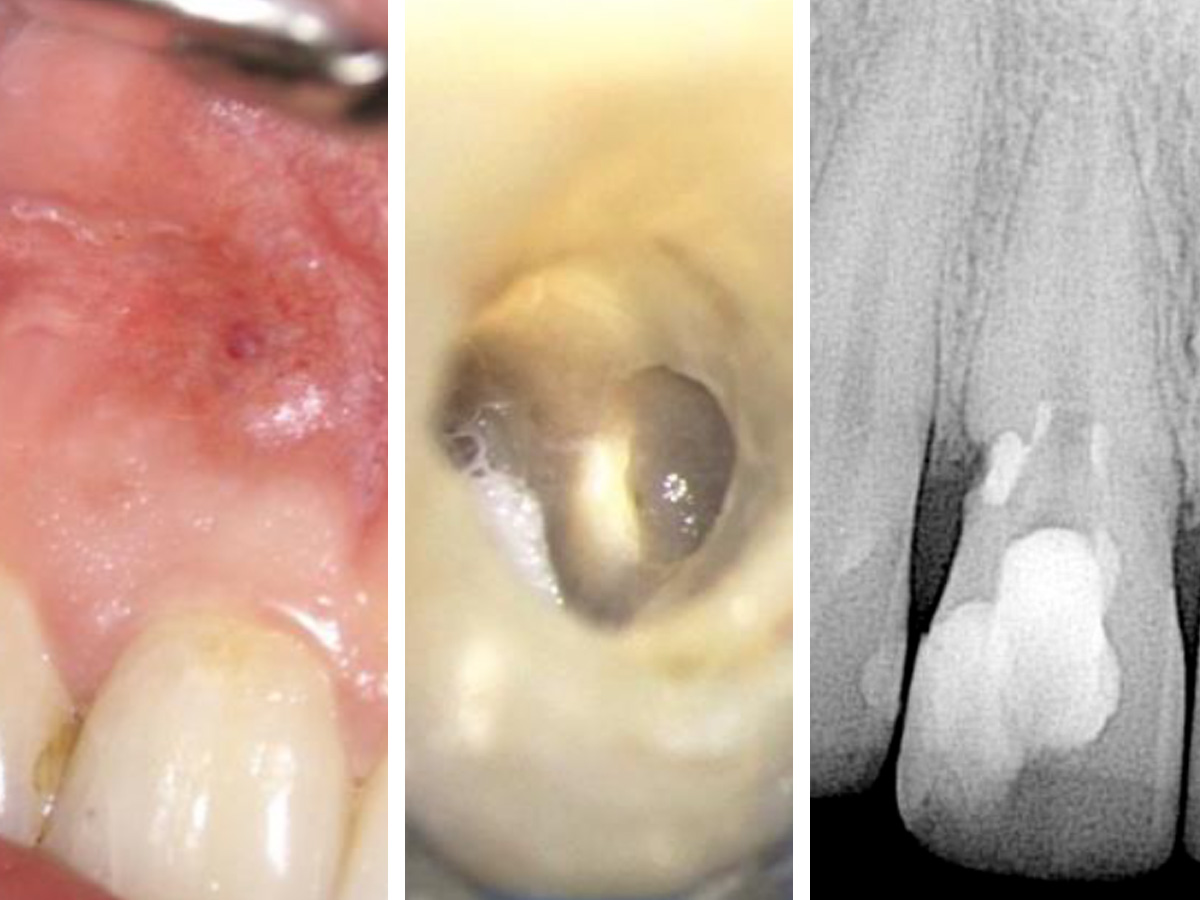

Der geöffnete Zugang zeigt die Gutta-Percha im koronalen Kanal und das BC Putty im resorptiven Defekt. Das Röntgenbild zeigt die Situation direkt nach der Behandlung.

Abbildung 5

Die klinische Sondierung war normal und die Fistelöffnung verschwunden. Bei den Follow-Ups nach sechs bzw. 15 Monaten zeigten sich knöcherne Struk turen im resorptiven Defekt.

Als die Patientin nach zwei weiteren Wochen wiederkam, war keinerlei Fistelbildung zu diagnostizieren, das biokeramische Putty war immer noch an der modellierten Stelle vorhanden und schien den Defekt gut zu versiegeln. Der Wurzelkanal wurde fertiggestellt und die Zugangskavität mit einem Komposit versiegelt (Abb. 4).

Bei den Follow-Ups nach sechs bzw. 15 Monaten war die Patientin noch immer symptomfrei. Die Sondierung war normal und es lag keine Fistelöffnung vor. Zudem waren knöcherne Strukturen im resorptiven Defekt erkennbar (Abb. 5).